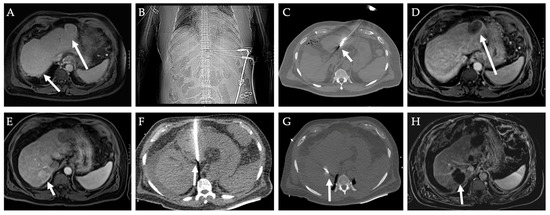

2.3. Computed Tomography, Cone-Beam CT, and CT Fluoroscopy

2.4. MRI